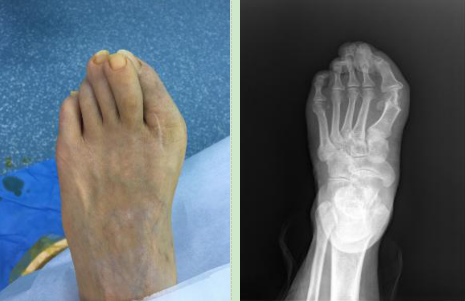

1.传统踇外翻手术复发微创手术修复后对比图

术前:

术后: